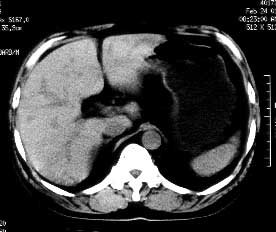

男性,53岁,腹痛、腹泻3天。体检:肝大,达肋下5cm,质中,无压痛。

ct平扫:肝脏密度普遍不均匀减低,ct值6-18hu,肝内血管相对显示为高密度。

ct诊断:脂肪肝。

患者经护肝治疗3个月后ct复查,肝实质密度恢复正常。